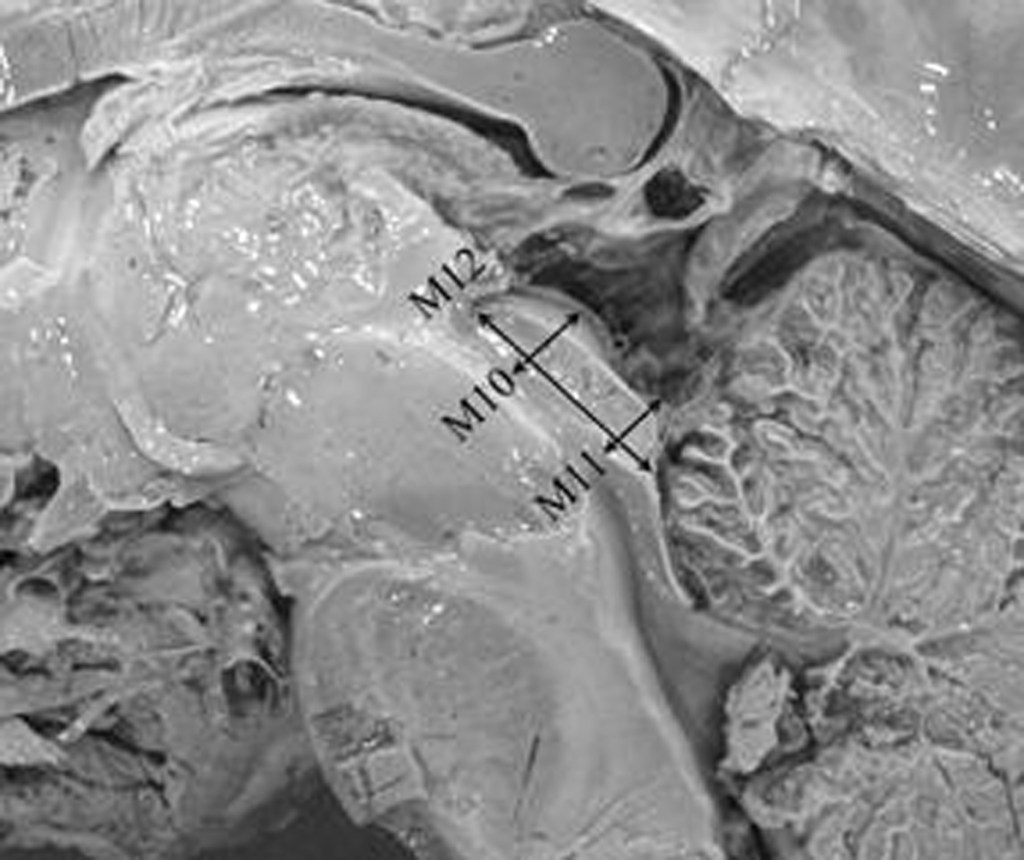

Morphometry of the anterior third ventricle region as a guide for the transcallosal-interforniceal approach. Erturk M, Kayalioglu G, Ozer MA. Neurologia Medico-Chirurgica 44:288-292, 2004. [Link to paper]

Morphometry of the anterior third ventricle region as a guide for the subfrontal (translaminaterminalis) approach. Erturk M, Kayalioglu G, Ozer MA. Neurosurgical Review 26;249-252, 2003. [Link to paper]